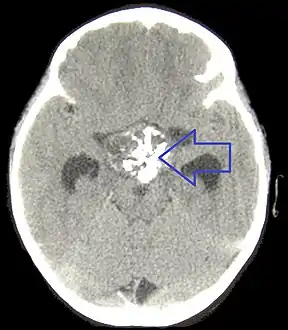

If one of these tests shows a deficiency of hormones produced by the pituitary, magnetic resonance imaging (MRI) scan of the pituitary is the first step in identifying an underlying cause. MRI may show various tumors and may assist in delineating other causes. Tumors smaller than 1 cm are referred to as microadenomas, and larger lesions are called macroadenomas.[1] Computed tomography with radiocontrast may be used if MRI is not available.[8] Formal visual field testing by perimetry is recommended, as this would show evidence of optic nerve compression by a tumor.[8]